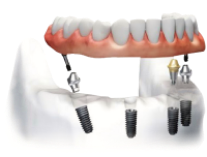

Имплантация All-on-4:

4 импланта + несъёмный протез за 1 день

В чём заключается технология All-on-4

Мы устанавливаем 4 импланта и несъёмный протез на всю челюсть за 1 приём